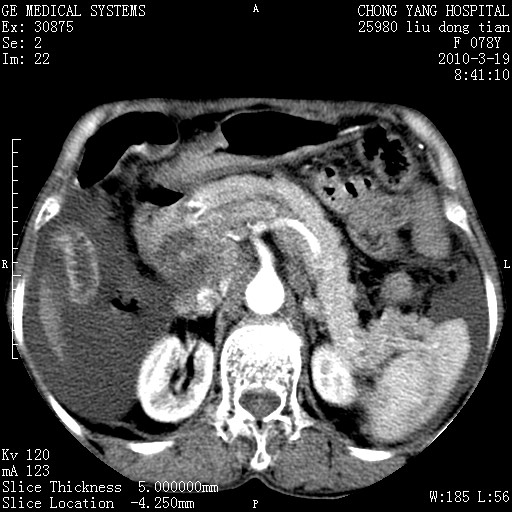

标题: CT25199:F 78Y 腹胀半年 消瘦乏力 [打印本页]

胆囊壁增厚并明显强化,胆囊癌伴多发转移瘤可能性大,淋巴瘤不除外,右肾囊肿,胸腹水.

考虑nhl,肝、脾、腹膜腔及腹膜后多发淋巴结受侵,腹水,右肾囊肿,慢性胆囊炎,右侧少量胸腔积液。

胰头有肿块形成,胰头ca伴肝脾、腹膜腹膜后转移

胆囊有软组织影有强化,支持胆囊癌,肝脾、腹膜后淋巴结转移。

nhl的淋巴结多围绕主动脉,而且主动脉会移位,所以不考虑nhl。

分开来讲:肝左叶、尾叶病灶有不均强化像肝癌;

脾脏病灶无强化,像多发囊肿或淋巴管瘤,不除外淋巴瘤(低强化);

胆囊增生性病变:胆囊癌,腺肌增生症,慢性胆囊炎;

肝门、胰腺头、腹膜后多个团块: 淋巴瘤,转移;

腔静脉肝内段细小有无布加可能?

一元论最好了 淋巴瘤所致改变; 胆囊癌转移不像,胆囊周围肝组织清晰,肝癌淋巴结转移?三元论都不止。

最后报的胰头癌多发转移,脾脏单独考虑囊肿或淋巴管瘤。